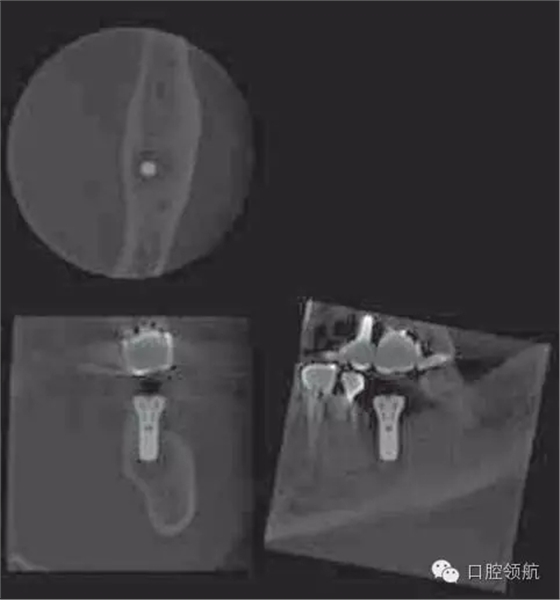

懷疑是因為植入術(shù)前進行5 根管治療導致的根尖周炎,拍攝牙片,根尖部未見異常,也沒有叩痛等癥狀(圖4)。

術(shù)后第18天,進行CBCT的確認(圖5),種植體周圍發(fā)現(xiàn)不透過影像,而且種植體有松動,因此在浸潤麻醉下拔除(圖6~圖8)。

圖5 術(shù)后18天CBCT的影像。